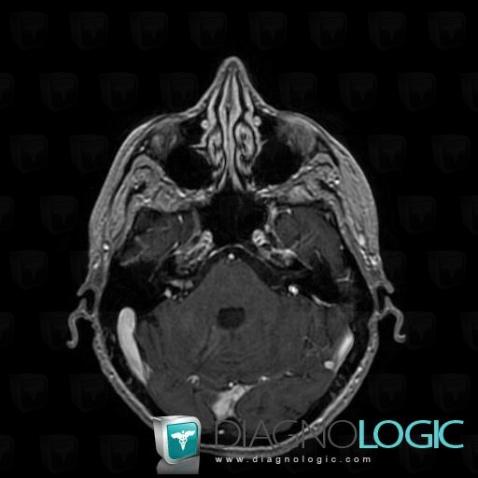

Les images ci-dessous illustrent ce dossier pour les diagnostics Carcinose méningée, Méningite carcinomateuse, pour les modalités (IRM)

Voici les informations spécifiques à l'image clé ci dessus:

- Diagnostic Carcinose méningée, Localisation(s) Nerfs VII VIII, comportant les gammes Lésion des nerfs VII / VIII

Voici les informations spécifiques à l'image clé ci dessus:

- Diagnostic Méningite carcinomateuse, Localisation(s) Espaces peri cérébraux infratentoriels, comportant les gammes Lésion extra axiale infra tentorielle